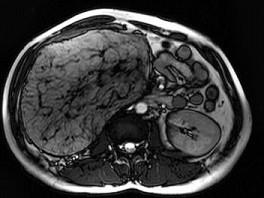

问题 男,30岁。右侧腹部包块渐增大,伴胀痛1年余。MRI检查见巨大包块,最可能的诊断是 ( )

选项 A、右肾巨大血管瘤 B、右肾错构瘤 C、右肾髓样脂肪瘤 D、右肾畸胎瘤 E、右侧肾上腺腺瘤

答案 C